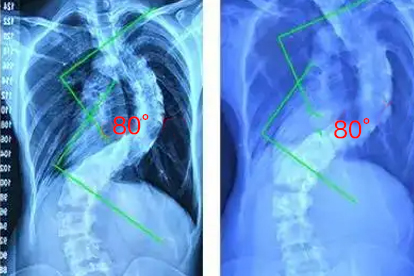

需警惕的是某些病理性因素可能同时引发脊柱变形和卧位不适。马凡综合征患者因结缔组织缺陷易合并脊柱侧弯,神经纤维瘤病可能伴随椎体发育异常。这类患者睡眠时需使用符合人体工学的支撑垫,避免侧卧压迫凸侧。青少年若出现双肩不等高、肋骨隆起等体征,应及时进行脊柱全长X光检查,排除进行性加重的结构性侧弯。

日常应保持仰卧与侧卧交替的睡姿,选择高度适中的枕头和中等硬度床垫。发育期儿童建议每天进行游泳、单杠悬吊等对称性运动,避免单侧负重活动。已确诊脊柱侧弯者需遵医嘱佩戴矫形支具,定期复查Cobb角变化情况,必要时考虑手术矫正。